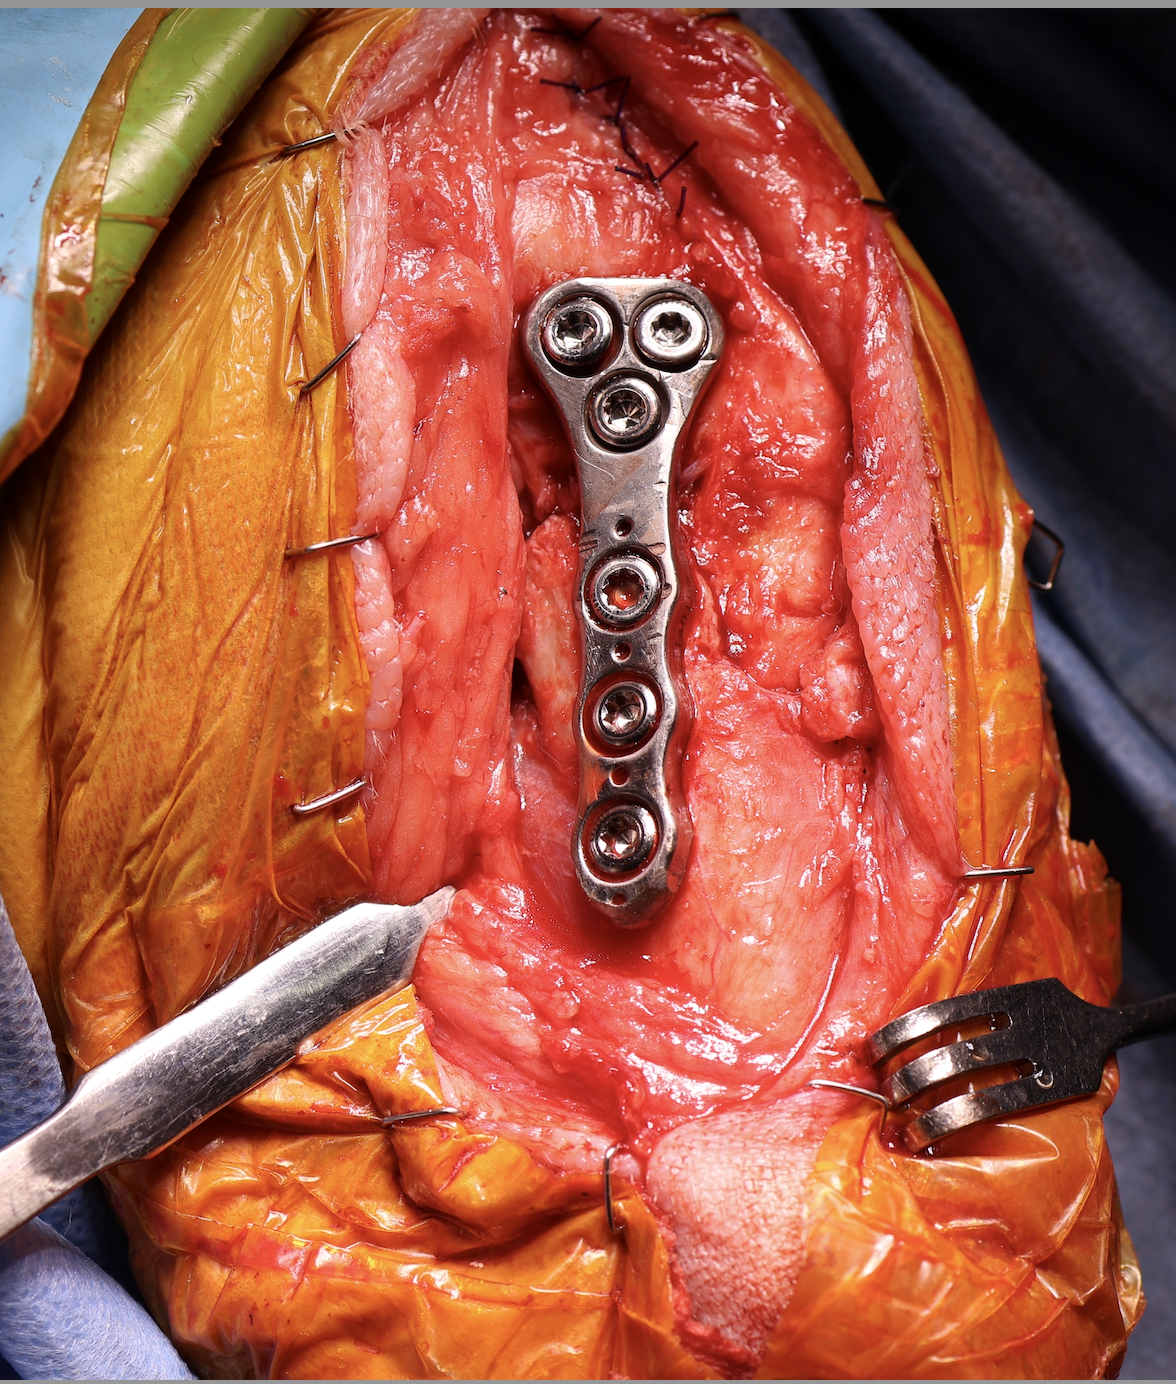

性の前十字靭帯断裂の中型犬にCBLOで安定化を実施しました。慢性経過のためミディアルバトレスが分厚くなって触知することが可能です。また関節内を探査すると、内側半月板の尾側領域はダブルバケットハンドルという状態で亀裂が2ヶ所確認されました。しばらくは安静が必要です。